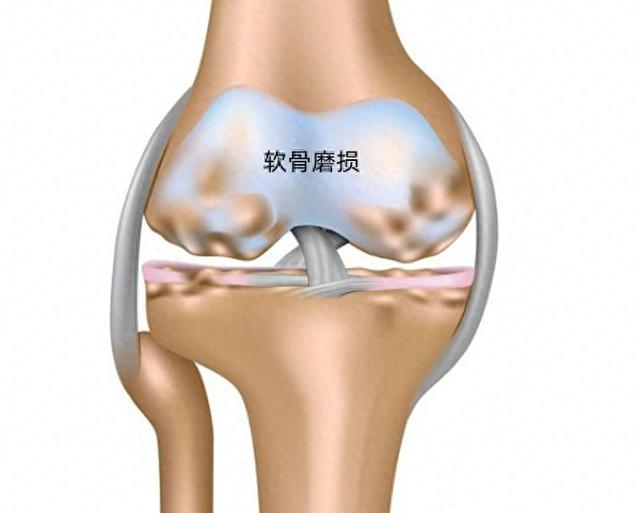

膝盖疼痛和不适有多种表现形式:钝痛,剧烈刺痛,还可伴有僵硬,发热和肿胀,有些还伴有响声,上了岁数的人容易患上了关节炎,以骨关节炎最为常见,类风湿关节炎次之。骨关节炎是一种退行性关节病。也被称为关节“磨损”疾病,主要是关节中起缓冲作用的软骨断裂或磨损引起的。

关节炎引起的膝关节疼痛膝骨关节炎的典型症状是关节疼痛和僵硬,同时伴有活动范围受限。它的疼痛来源于关节中的弹性软骨损失,继而膝关节软骨变薄,关节表面变粗糙,骨头和骨头摩擦,膝盖不能像正常情况下那样平稳地活动,患者会感到疼痛,僵硬和炎症。通过X光通常能发现软骨的损失,但关节炎疼痛的轻重和表现形式多种多样,具体症状取决于关节退化的程度和性质,还有患者的体重,体质以及对疼痛的个人感受。